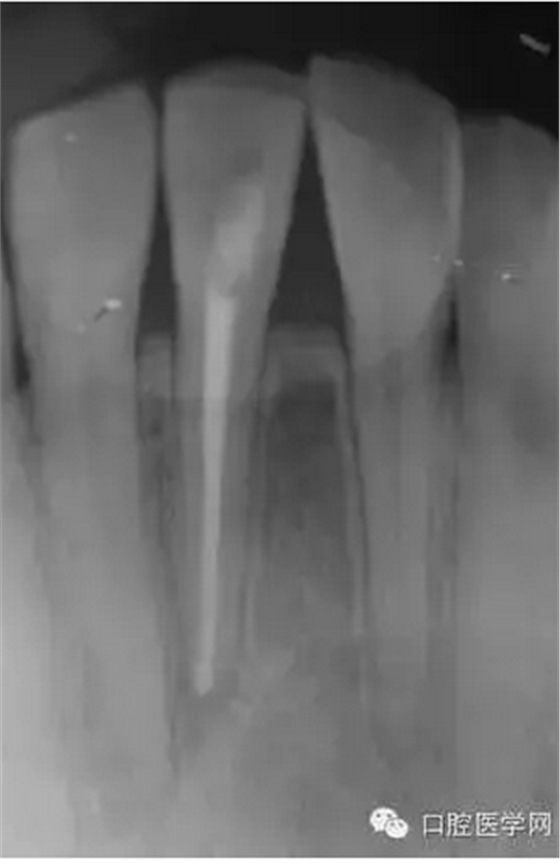

23歲女性患者,下頜右前牙的唇側(cè)有嚴(yán)重腫脹和疼痛。相應(yīng)部位有過外傷史,但記不起是什么時候了。放射線照片顯示以右下頜中切牙為中心,有波及右下側(cè)切牙及左下中切牙的大范圍的根尖周病變,臨床檢查時,無齲壞,只發(fā)現(xiàn)右下中切牙略有變色,牙髓活力檢查(電子牙髓檢查及冷檢查)發(fā)現(xiàn),右下中切牙無反應(yīng),而鄰近齒表現(xiàn)為正常。判斷大范圍的根尖周病變的原因是受過外傷的右下中切牙的牙髓壞死,受周邊環(huán)境影響,發(fā)展為急性根尖周膿腫。

(圖 1) 初診的放射線照片